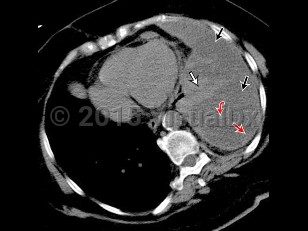

Transudative pleural effusions are due to conditions in which there is an imbalance in hydrostatic and oncotic forces such as with heart failure, cirrhosis, or nephrotic syndrome.

Exudative effusions are due to inflammation from infection or noninfectious etiologies, injury, malignancy, and impaired lymphatic drainage. The primary method of distinguishing transudate from exudate is Light's criteria: